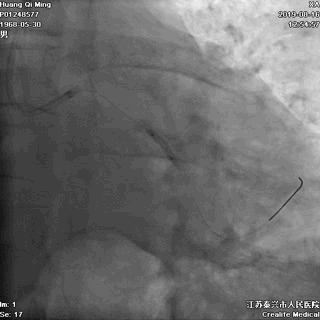

LCX PCI过程

导丝通过病变

球囊扩张,PTCA

支架定位和植入

高压扩张使支架贴壁

LCX植入后即刻效果满意